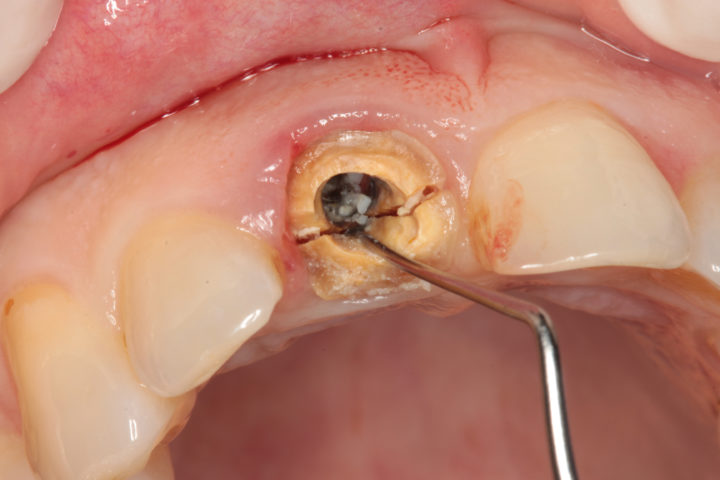

Situazione iniziale:

Incisivo superiore gravemente fratturato e non recuperabile. La frattura coinvolge la radice del dente, rendendo necessaria l’estrazione e la sostituzione con un impianto dentale.